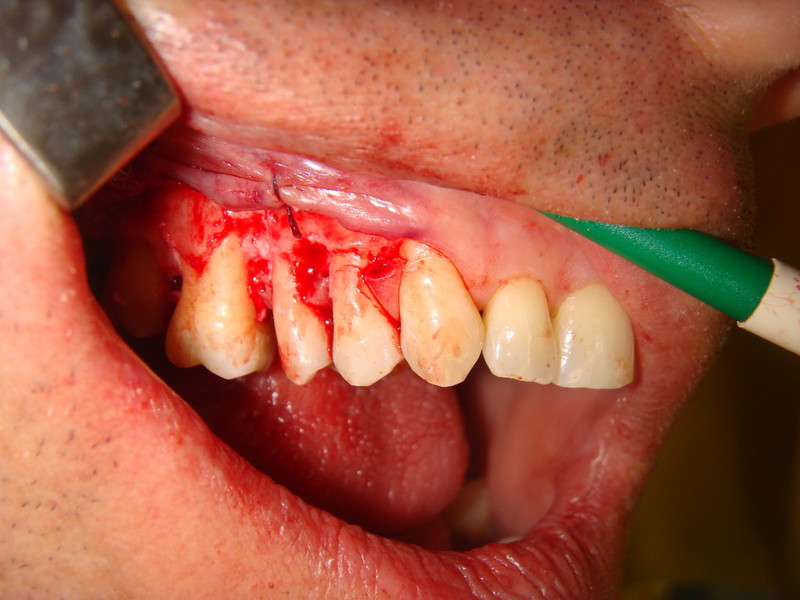

Rigenerazione difetto parodontale di un canino inferiore con materiale eterologo